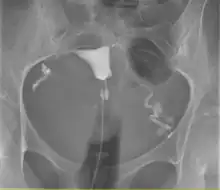

Hystérographie à l’aide d'un cathéter (ligne partant du bas) mettant en évidence la cavité utérine (triangle au centre) et les trompes de Fallope (à gauche et à droite) (2)

L’hystérographie est la radiographie de l’utérus et des trompes, réalisée chez un radiologue.

— (Alain Tamborini, 800 questions au gynécologue, 2009)L’hystérosalpingographie, également connue sous le nom d’hystérographie, est un examen médical crucial dans le domaine de la gynécologie. L’hystérographie est un outil diagnostique précieux pour évaluer la santé reproductive des femmes.